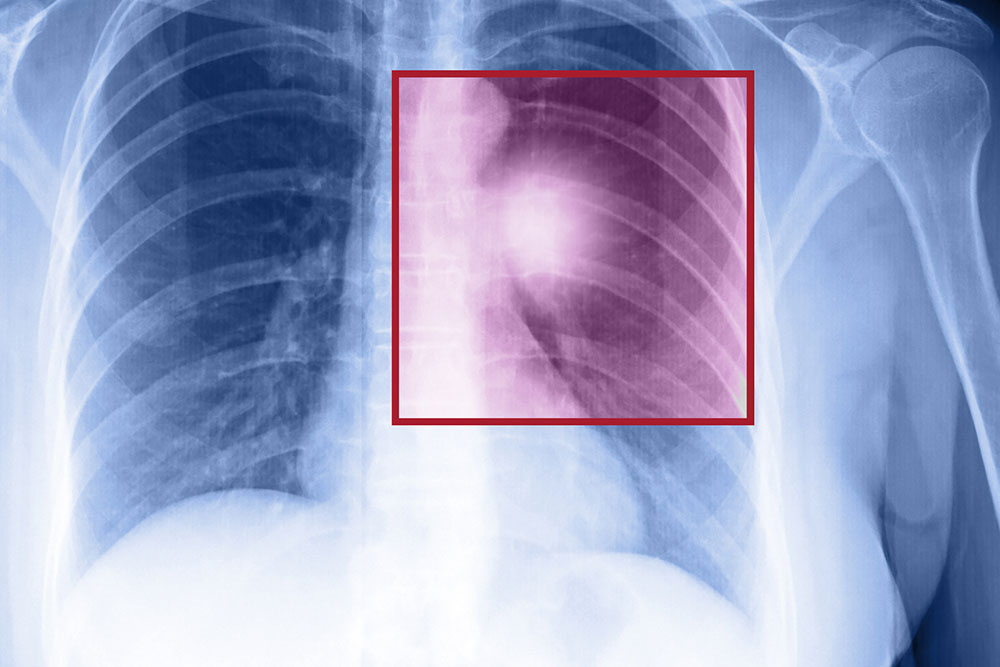

• Chest X-ray which provides detailed images of the lungs.

• CT scan which produces clear pictures of the cross section of the lungs.